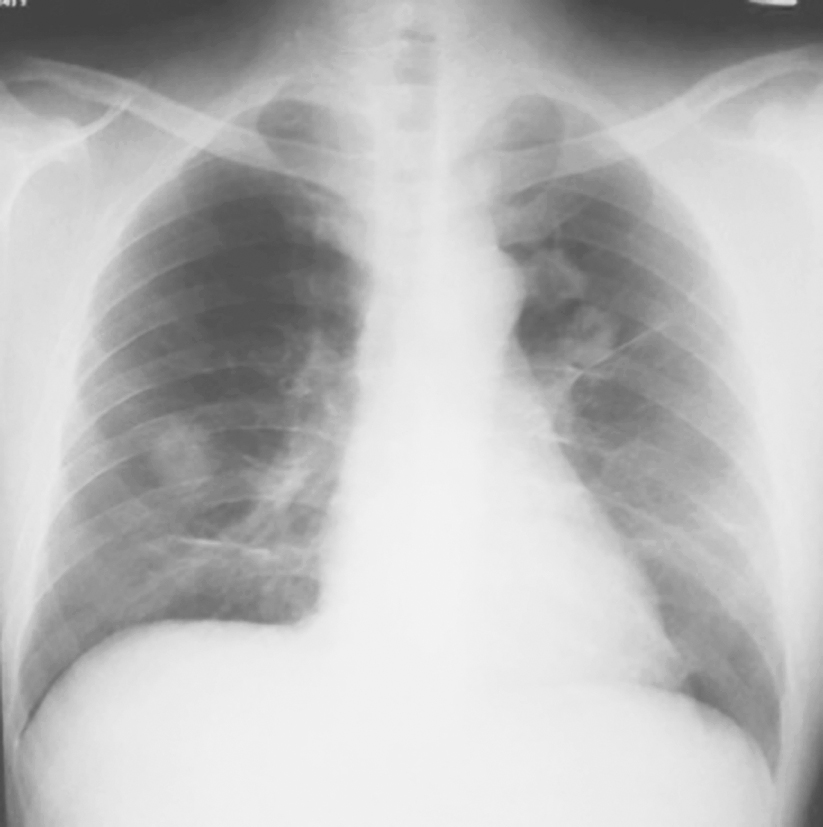

图4|X线胸片表现(2009-11-17)

X线胸片示双肺多发结节影